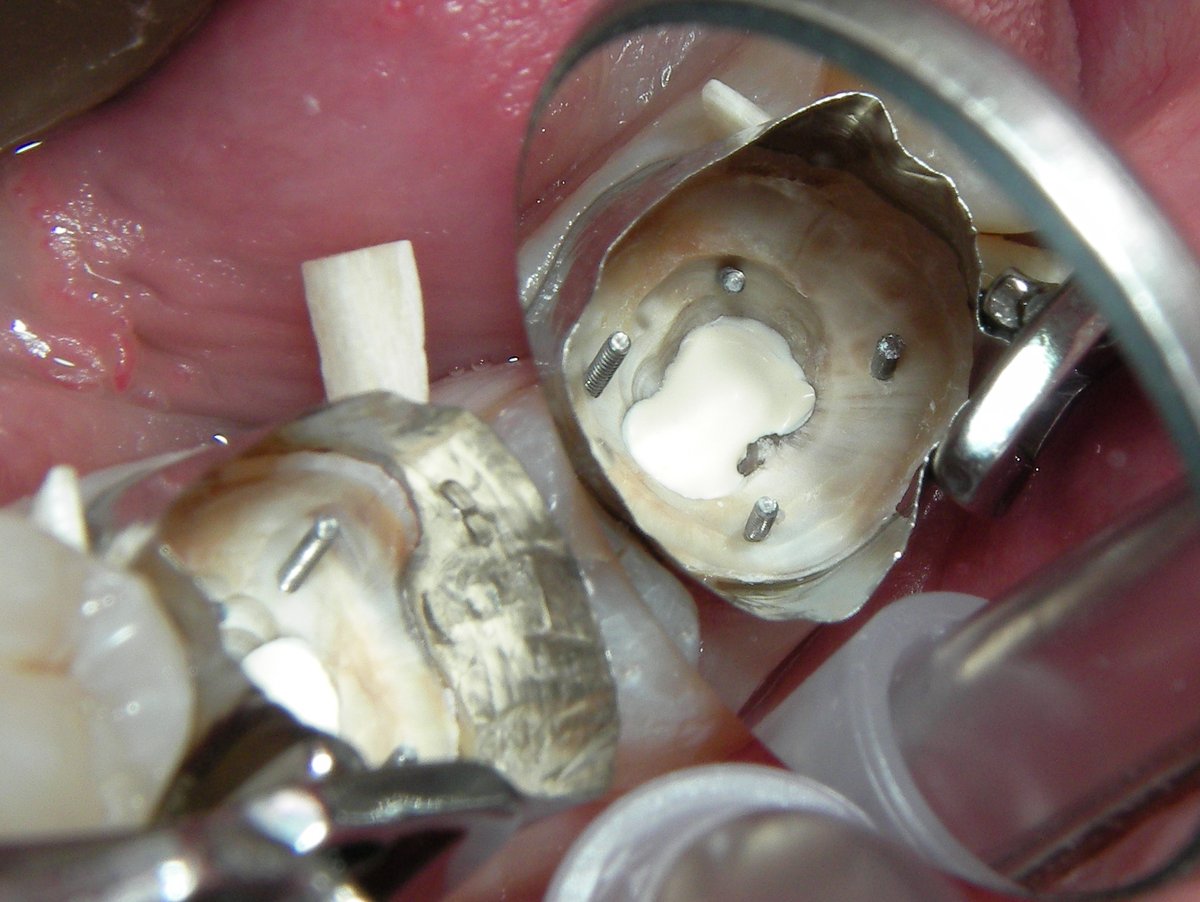

Zur Verankerung werden kleine Schrauben (Dentinstifte) in das verbleibende Dentin eingedreht. Sie ragen aus dem Zahn heraus und geben der Aufbaufüllung zusätzlichen Halt. Als Aufbaumaterial bewährt sich Amalgam durch seine sichere Verarbeitung und Festigkeit (1).

Das Aufbaumaterial wird schichtweise eingebracht und zwischen den Stiften kondensiert. Ziel ist eine geschlossene, ausreichend hohe Zahnwand, die später der Kofferdamklammer Halt gibt.